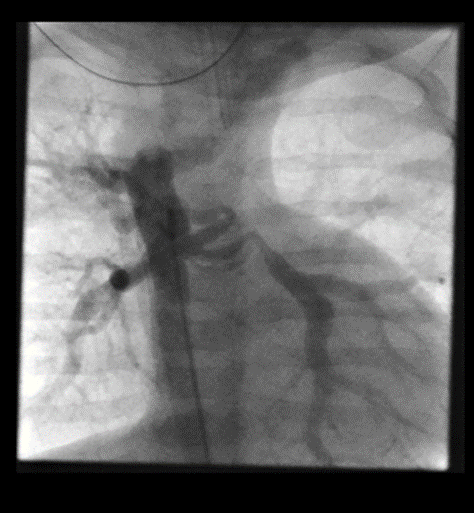

- Cardiac catheterization. An interventional cardiologist inserts a thin tube with a tiny camera through a blood vessel in the groin or arm and guides it to the heart. This shows images of the heart structures, vessels and any blockages.

Our advanced imaging techniques clearly define the anatomical details of the major aortopulmonary collaterals and any existing heart anomalies.

We use 3D and virtual reality models to predict procedure outcomes. These tools help design the right cardiac catheterization interventions and the best surgical approach.